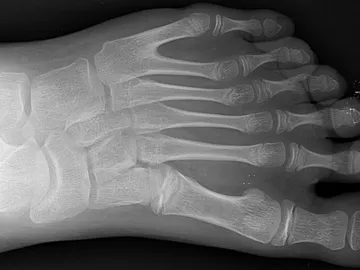

Tener un órgano o una parte del cuerpo extra es más común de lo que pensamos